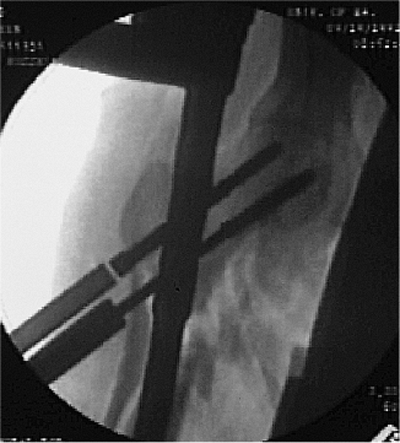

Figure 20.19. A,B.

Inferior guide wire is inserted, and correct placement to within 5-mm of subchondral bone and correct neck-shaft alignment are confirmed. |